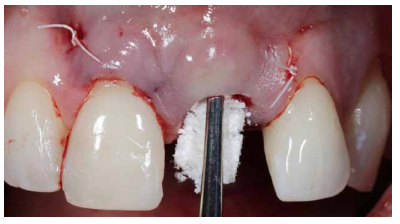

Así mismo, se han establecido diferentes protocolos para el manejo del sector estético anterosuperior, que se suman al acto de la colocación inmediata del implante y la corona provisional, donde se incluyen la colocación de un material no reabsorbible entre el IOI y la cortical vestibular para minimizar el posible colapso, así como el manejo de los tejidos blandos periimplantarios8-11.